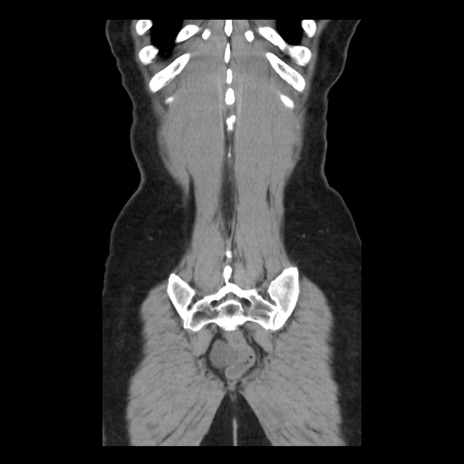

横断像

矢状断像

【症例】 50歳代女性

【主訴】 腹痛

【現病歴】前日生レバーを食べた。今朝に排便あり。 昼前に突然発症の腹痛を生じ、当院救急外来を受診した。

【既往歴】 子宮筋腫にてで子宮全摘後

【身体所見】 意識清明、腹部:平坦、軟、下腹部やや左を中心に圧痛・反跳痛あり、筋性防御あり

【データ】WBC 7800、CRP 0.07